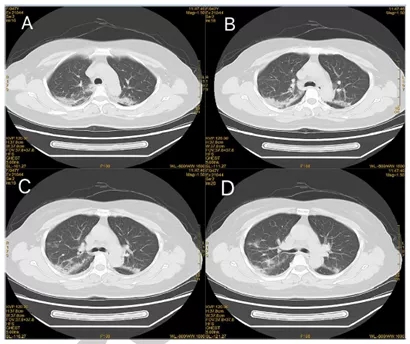

患者于2020年1月29日转至深圳大学总医院进行进一步隔离和临床观察。入院时(发病第9天)头痛、咳嗽加重,但体温(36-37.2℃)、氧饱和度(99%)相对正常。血液检查显示白细胞计数正常(5.81×109/L),淋巴细胞计数下降(0.91×109/L)。胸部CT显示双侧磨砂玻璃样阴影[见CT结果图]。